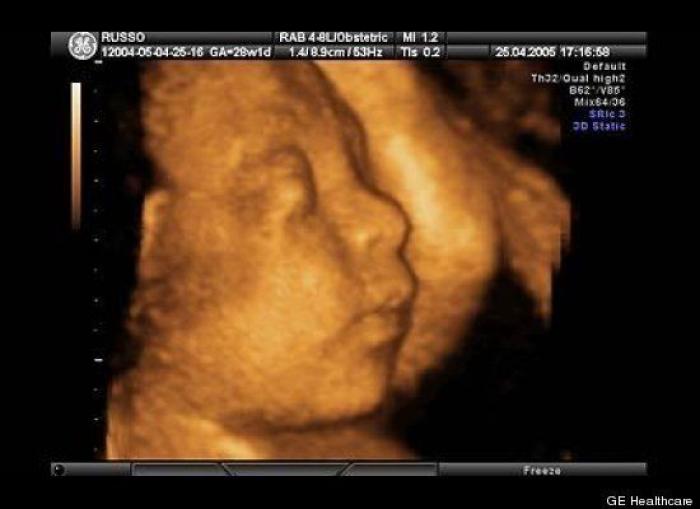

En esta galería puedes ver en fotos como es el desarrollo de un feto de semana en semana:

Desarrollo del feto, en fotos